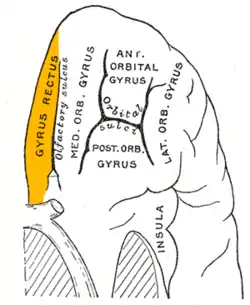

Hemisferio cerebral izquierdo, vista inferior: localización del giro recto en la superficie orbital. | ||

Animación la circunvolución recta se muestra en rojo.

Animación la circunvolución recta se muestra en rojo. Superficie basal del del cerebro. La circunvolución recta se muestra en rojo.

Superficie basal del del cerebro. La circunvolución recta se muestra en rojo. Circunvolución recta vista anteriormente en el centro.

Circunvolución recta vista anteriormente en el centro.